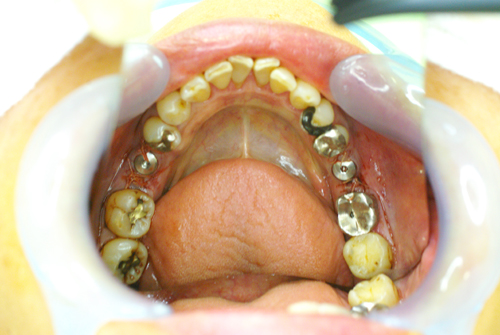

術後の口腔内写真です

オペ直後の口腔内写真となります。この患者様は遠方からの来院のため、抜糸をしなくていいように吸収性の縫合糸での縫合となりました。